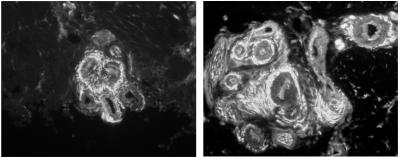

To analyze the nerve endings, Drs. Rice, Albrecht, and postdoctoral researcher Dr. Quanzhi Hou, used their unique microscopic technology to study small skin biopsies (less than half the size of a pencil eraser) collected from the palms of fibromyalgia patients, who were being diagnosed and treated by Drs. Argoff, Wymer, and Storey. The study was limited to women, who have over twice the occurrence of fibromyalgia than men. What the team uncovered was an enormous increase in sensory nerve fibers at specific sites within the blood vessels of the skin. These critical sites are tiny muscular valves, called arteriole-venule (AV) shunts, which form a direct connection between arterioles and venules (see diagram).